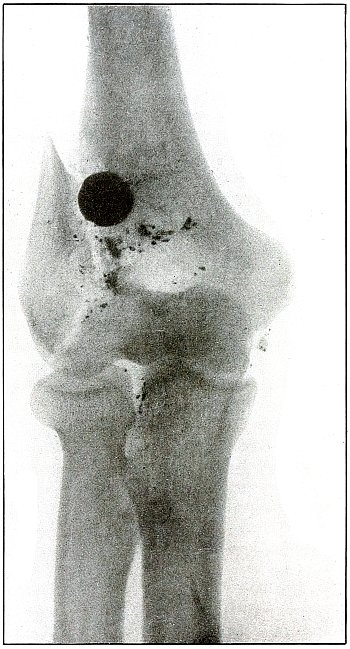

| 18. |

Gunshot fracture, elbow |

46 |

| 19. |